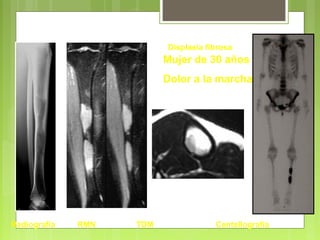

Radiografía RMN TDM Centellografía

Mujer de 30 años :

Dolor a la marcha

Displasia fibrosa